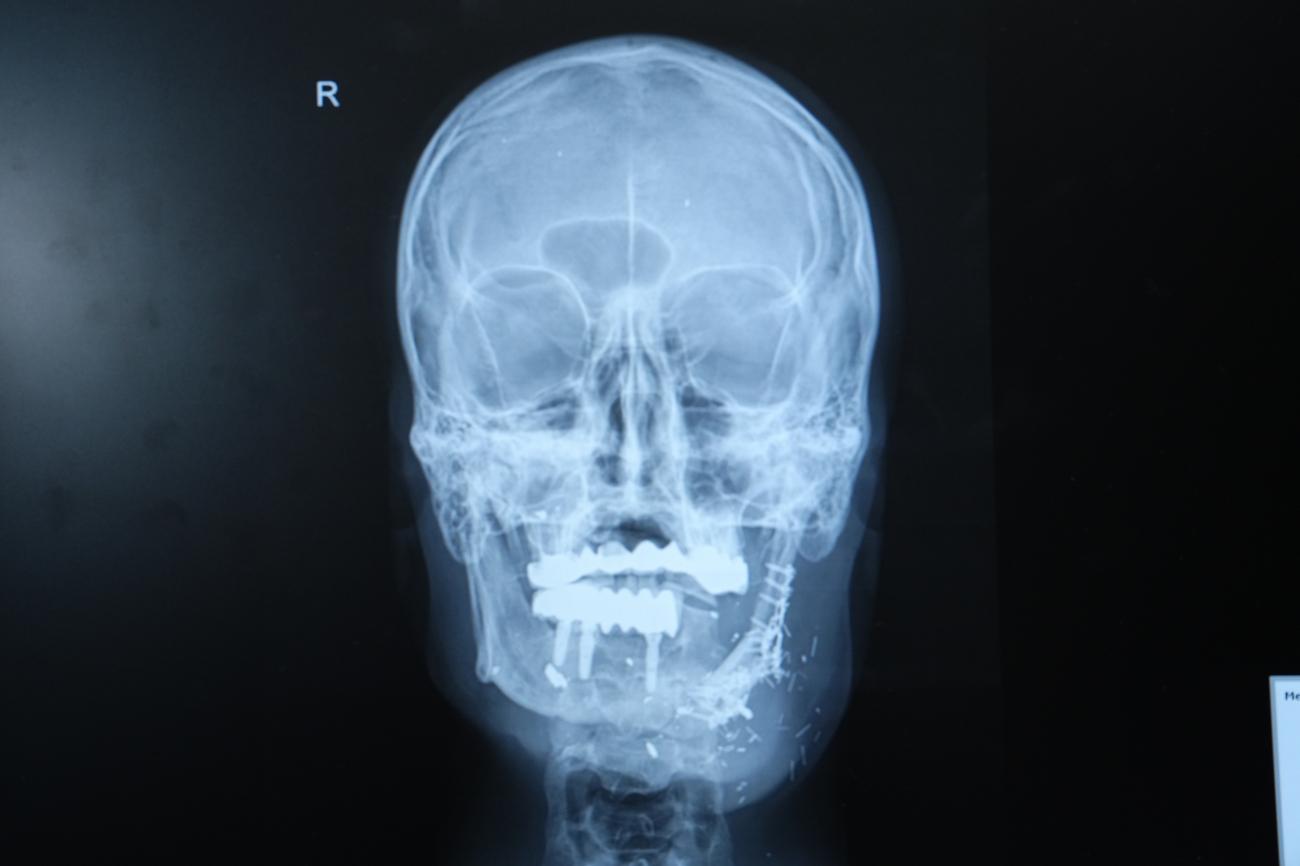

Hastanın durumunun oldukça komplike olduğunu dile getiren Doç. Dr. Özkan, “Hastamız ateşli silah yaralanması sonrası çenesinin yarısını kaybetmişti. Daha önce farklı merkezlerde ameliyat olmuş fakat nakiller başarısız olmuştu. Hem çene bütünlüğünü sağlamak hem de ileride implant yapılabilecek sağlam bir kemik dokusu oluşturmak gerekiyordu. Hastanın bacağından aldığımız kemiği mikrocerrahi yöntemle çeneye naklettik. Damarlara bağlantı yaptık, plaklarla sabitledik. Bu sayede hem fonksiyonel hem de estetik olarak başarılı bir sonuç elde ettik” diye konuştu.

Doç. Dr. Özkan, bu tür vakalarda mikrocerrahinin önemine dikkat çekerek, “Kompozit doku eksikliklerinde vasküler kemik transferi bize büyük avantaj sağlıyor. Hastamız şu an kendi beslenmesini sağlayabiliyor. Önümüzdeki süreçte kemik iyileşmesini tamamladıktan sonra diş implantları yerleştireceğiz ve hastamız çok daha rahat beslenebilecek.” şeklinde konuştu.